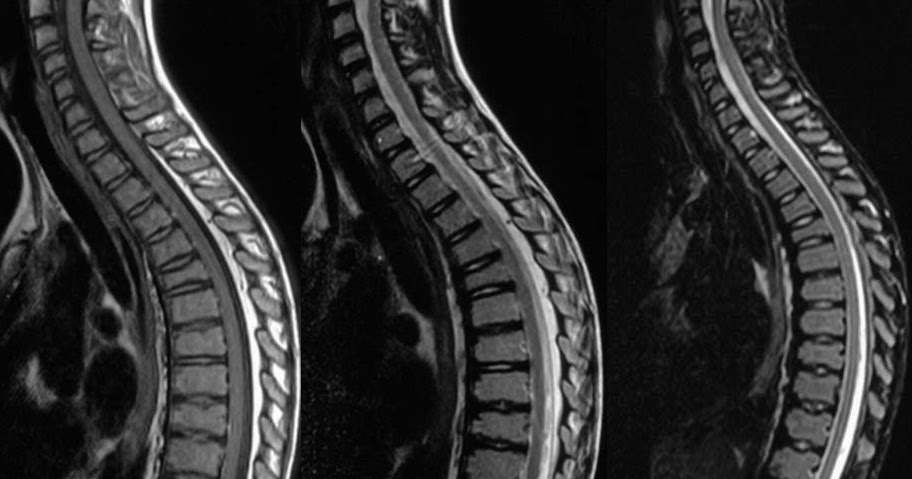

Neuroradiology On the Net: Scheuermann's disease (adolescent kyphosis)

Neuroradiology On the Net: Scheuermann's disease (adolescent kyphosis) from 3.bp.blogspot.com

@article{swischuk1998diskdd, title={disk degenerative disease in childhood:

Mri dorso lumbar region spine sagittal t2w images show: For most patients, scheuermann's disease runs a fairly benign course, with resolution of symptoms at skeletal maturity. Scheuermann, or scheuermann's, disease (juvenile kyphosis) is a deformity in the thoracic or thoracolumbar spine in which pediatric patients have an increased kyphosis along with backache and localized changes in the vertebral bodies. How do you get schmorl's nodes? Schmorl's nodes and modic changes (endplate mri signal change) on lumbar mri, back pain and physical function restrictions seem to be more prevalent among patients with scheuermann's disease. Most can form after a heavy loading incident or trauma which forces the nucleus part of the disc through the endplate instead of the outer part of the disc. Associated with irregular vertebral endplates, schmorl nodes, and loss of disc space height noted on sagittal imaging studies. This commonly results in back pain and is usually managed medically. Mri dorso lumbar region spine sagittal t2w images show: Schmorl's nodes are disc herniations in the spinal bone which are usually not painful. Scheuermann's disease describes a condition where the vertebrae grow unevenly with respect to the sagittal plane; The upper and middle areas of the spine, called the thoracic spine, consist of the 12 vertebrae below the seven that make up the cervical spine. Range of motion:the physician assesses the degree to which the patient can bend forward, back, and side to side. All had various disk problems including scheuermann's disease, schmorl's nodes and limbus vertebrae. With the help of some of the bravest and strongest people in the world, we, at the scheuermann's disease fund, have created a video project to let people know what it is like to live with scheuermann's disease, especially as we. In 1964, sorensen introduced the classic diagnostic criteria for sd of three consecutive vertebral bodies with anterior wedging of at least 5 degrees.5 additional imaging findings include endplate irregularities, commonly manifested as schmorl's nodes. Scheuermann's disease is a developmental disorder of the spine that is caused by abnormal growth of the vertebrae. Multiple and contiguous involvement of vertebral bodies, the anterior wedging, antero posterior elongation, associated schmorl's nodes, end plate irregularity and disc space narrowing. Small disc herniations through the endplates of the vertebrae (called schmorl's nodes). @article{swischuk1998diskdd, title={disk degenerative disease in childhood: Familial scheuermann disease is characterized by kyphotic deformity of the spine that develops in adolescence. Scheuermann's disease, schmorl's nodes, and the limbus vertebra: So scheuermann's disease inheritance remains uncertain, especially as these studies were based on restricted data coming from a few pedigrees. It affects less than one percent of the population and occurs mostly in children between the ages of 10 this forms pockets of disc material inside the vertebral body, a condition called schmorl's nodes. Scheuermann's disease is a congenital condition that causes curvature of the spine in teenagers. The diagnosis is usually made on plain film. Scheuermann kyphosis, also known as scheuermann disease, juvenile kyphosis or juvenile discogenic disease, is a condition of. 14 evidence of increased pain, suspicion of rapid progression, and/or neurologic compromise. Descriptions of schmorl's nodes note they generally do not cause many problems and they are in fact a pretty common side effect of general wear and tear on the spine. Scheuermann's disease causes some od the spinal vertebrae to grow in a wedge shape instead of a normal cylindrical shape. When scheuermann's disease is present, the thoracic area of the spine is overly curved from the side.